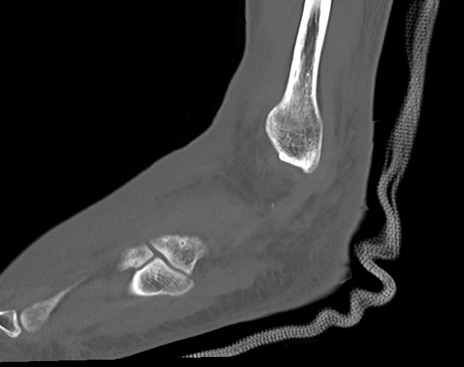

症例37 左足関節CT(矢状断像)

左足関節CT

横断像